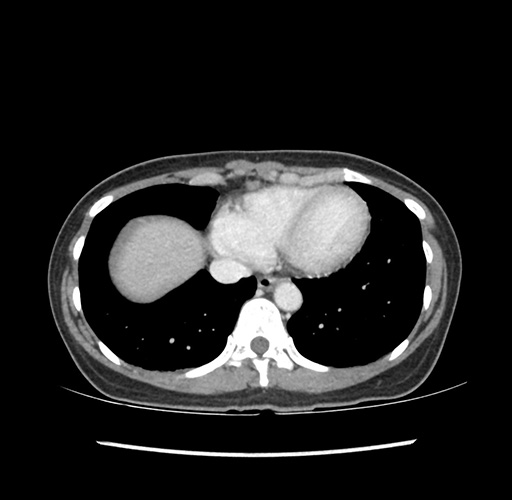

Imaging Analysis

Look through the patient's CT scan to identify any areas of concern for the necessary procedure.

Based on your CT findings, which issue(s) would give reason for "planned slowing down moment(s)" in this case?